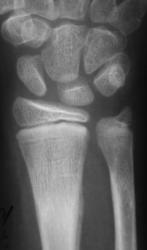

Пациент направлен в рентгеновский кабинет врачом хирургом, по поводу болей в дистальной трети предплечья. Пациент и его родители утверждают, что травмы не было.

Снимки с более высокой степенью разрешения.

Определяются локальные оссифицированные периостальные наслоения в н/3 диафиза лучевой кости, что-то наподобие дефекта со склеротическим контуром по передней поверхности кости. У меня три варианта: 1 - консолидированный перелом лучевой кости; 2 - патологическая перестройка (читала у Рейнберга, может встречаться в лучевых и локтевых костях, выглядит как консолидированный перелом); 3 - первично-хр. остеомиелит.

Больше похоже на срастающийся перелом.

Но т равмы не было. Чем может быть вызвана "одностороняя реакция надкостницы"?

Меня тоже смущает, и очень. Отправляйте к детским онкологам, пусть они контролируют. Основание: диафиз лучевой кости бульбообразно расширен ("поддут"), структура кости уплотнена муфтообразно/"пояском", менее выраженные, чем по переднему стенке кости, но аналогичные изменения отмечаются и по задней стенке диафиза, плюс периостальная реакция в прямой проекции.